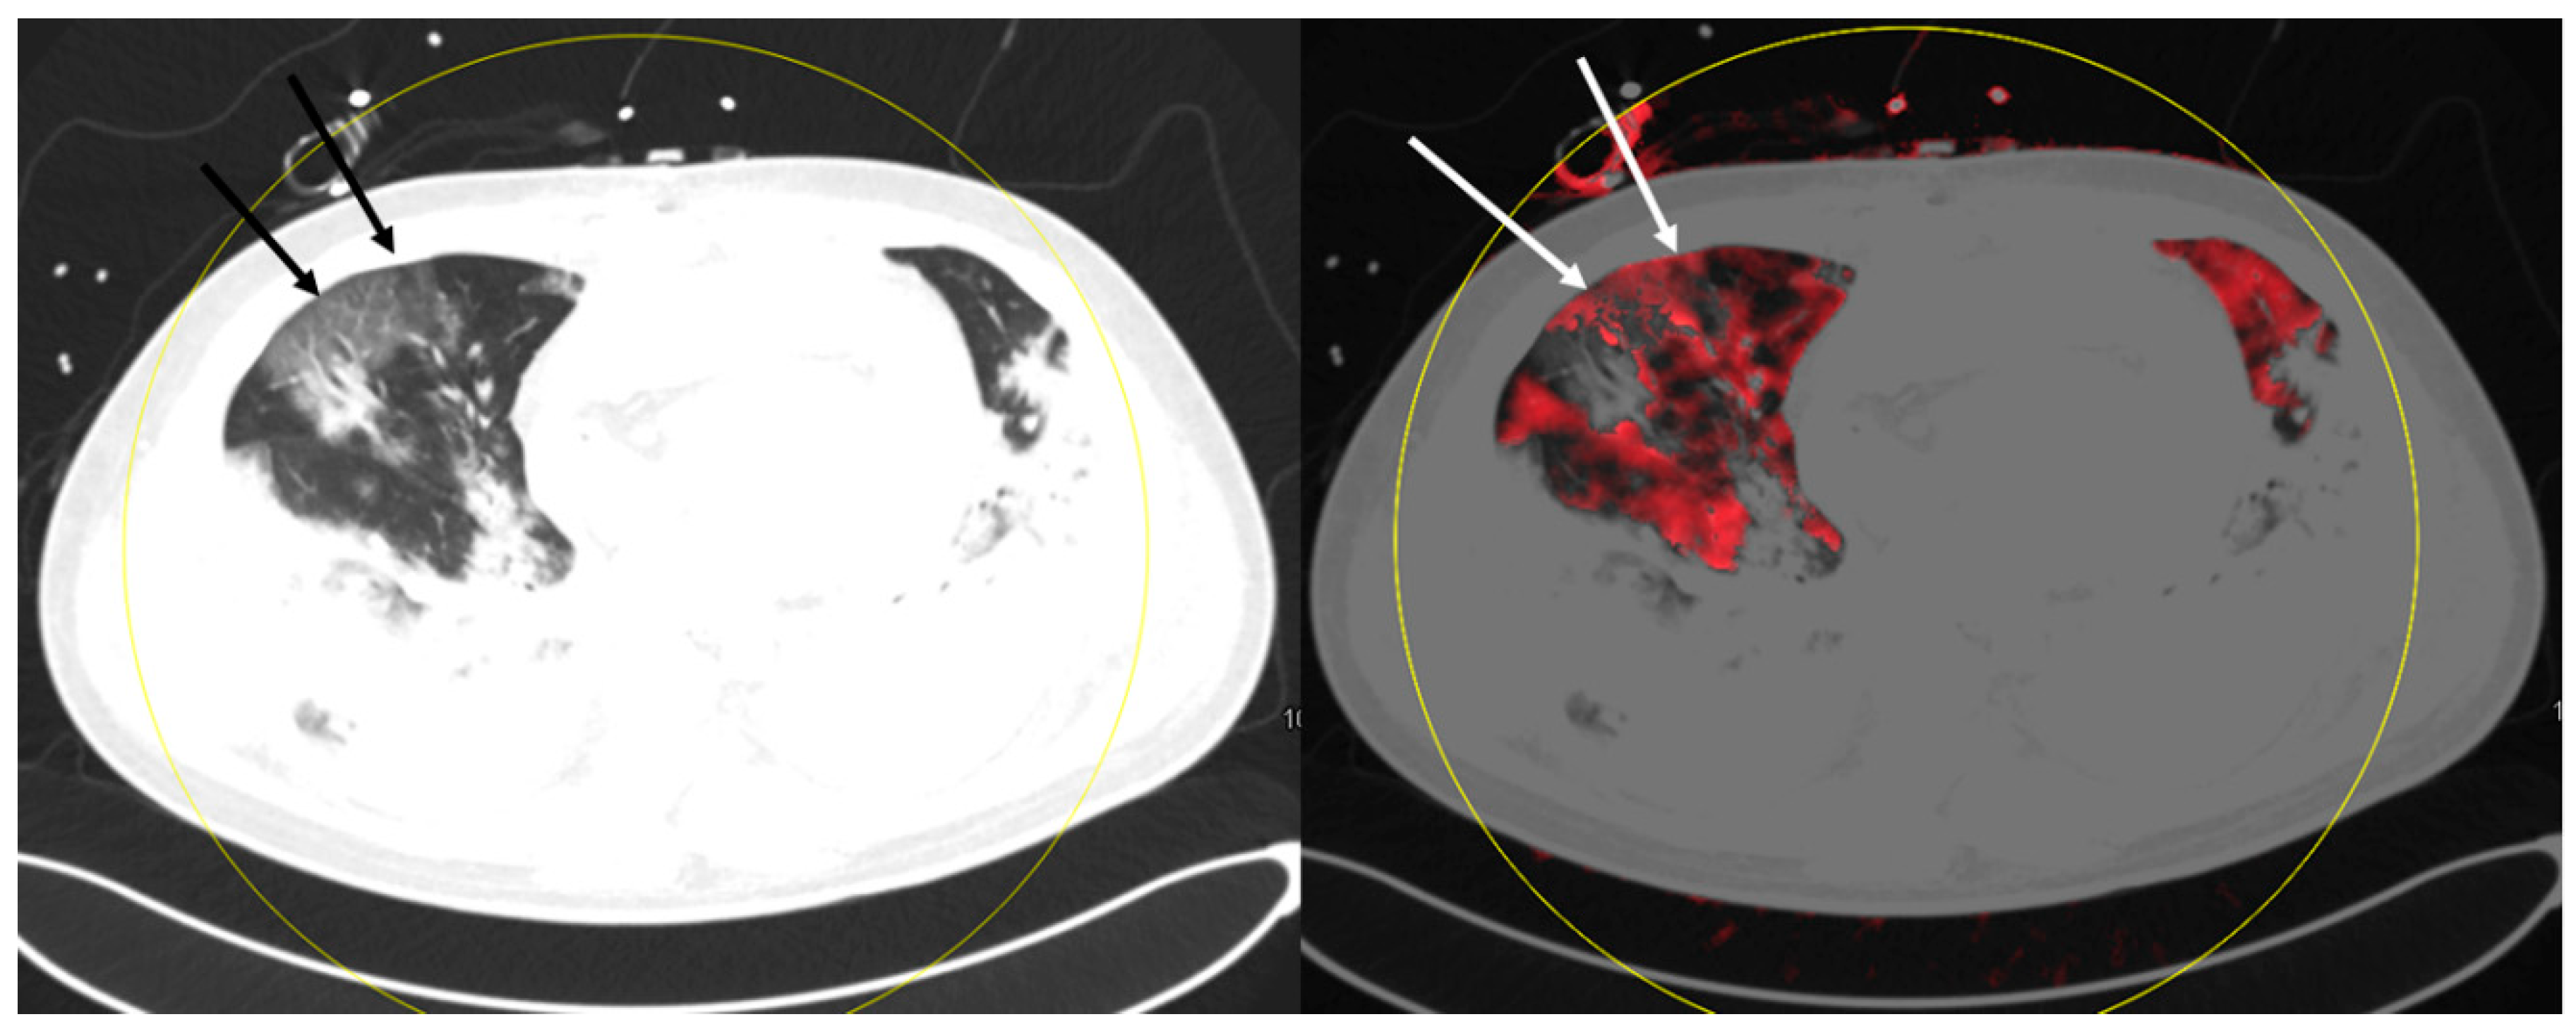

4. Discussion